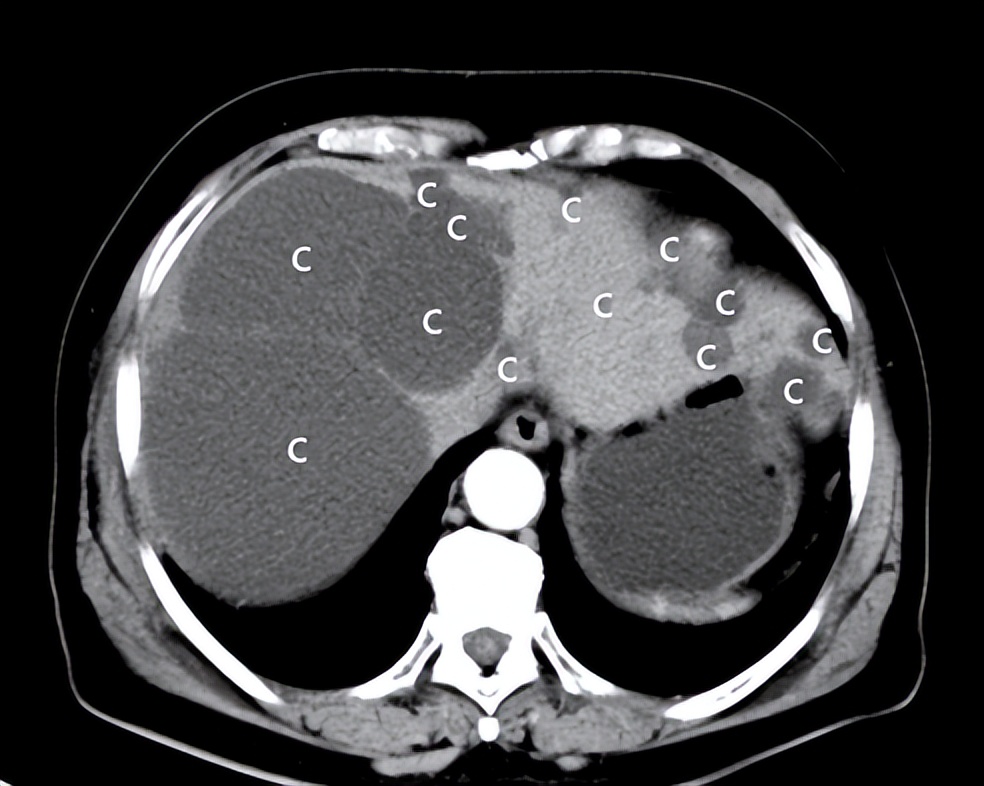

多发特大肝囊肿,先看图片

CT:肝内多发特大囊肿

CT:单个最大者>15cm

患者女性,50岁,多年前健康查体发现多发肝囊肿,最大者直径4cm。一年来感觉右上腹胀满,疼痛,食欲减退,来院检查,CT/超声提示:肝内多发肝囊肿,最大者直径>15cm。患者住院行:介入超声肝囊肿硬化治疗术。